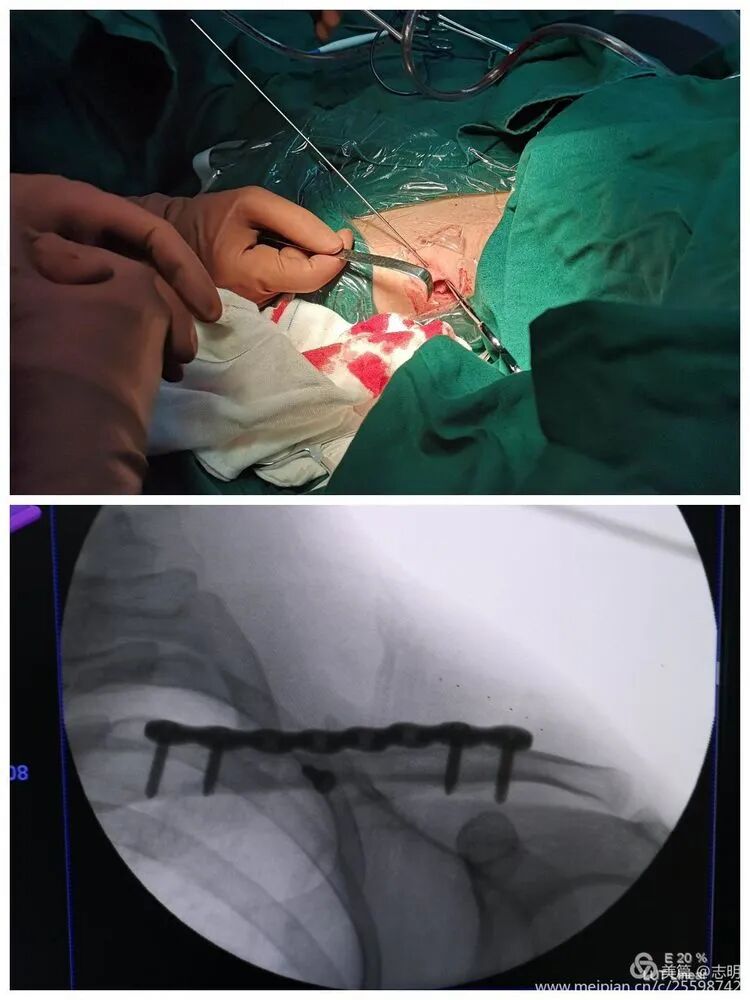

3. Fracture Reduction

-

Indirect Reduction Maneuvers:

This stage is often the most technically demanding aspect of MIPO. As articulated in the original content, "通过上抬肩部及调整上臂位置使断端初步复位" (By elevating the shoulder and adjusting the upper arm position, achieve preliminary reduction of the fracture fragments). The assistant plays a crucial role by dynamically manipulating the ipsilateral arm and shoulder to restore the clavicle's anatomical length, achieve proper alignment, and correct any rotational deformity.

Percutaneous Reduction Aids:

Various instruments can be employed percutaneously through small stab incisions to aid in reduction under fluoroscopic guidance. These include bone hooks, pointed reduction clamps, or small periosteal elevators. These tools allow for direct manipulation of fragments without extensive soft tissue exposure.

(Clinical image showing surgeon's hands manipulating the shoulder, likely assisting in reduction).

Temporary Fixation:

Once a satisfactory reduction is achieved, it must be temporarily secured prior to plate application. Percutaneous Kirschner wires (K-wires) are commonly used for this purpose. The seed content states: "对于长斜形等易临时固定的骨折,可经皮钻入1.5mm克氏针维持复位" (For long oblique fractures and others easily temporarily fixed, 1.5mm Kirschner wires can be percutaneously drilled to maintain reduction). Ensure that the K-wires are placed in a manner that does not impede subsequent plate placement or screw trajectory.

Screw Insertion:

- Begin by drilling and inserting screws in both the proximal and distal main fracture fragments through the small skin incisions. Utilize percutaneous drill guides and specialized screw drivers designed for MIPO techniques.

- Screw Length and Trajectory: Exercise extreme caution when selecting screw length to ensure adequate bicortical purchase without over-penetration, which carries a significant risk of damaging underlying neurovascular structures. Fluoroscopy, again in both AP and lateral/cephalic tilt views, is paramount for real-time assessment of screw trajectory and length.

(Image showing percutaneous drilling through a guide). -

(Fluoroscopic image depicting screw insertion).